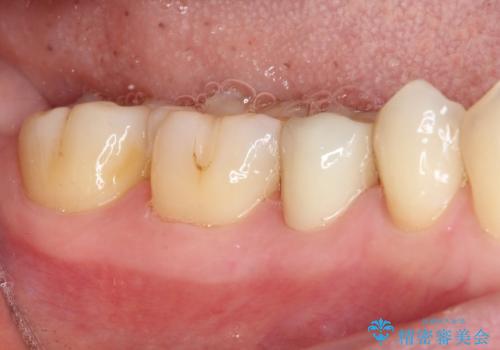

オールセラミッククラウンにて補綴することとしました。

しみる症状はなくなり、見た目もきれいになり、とても満足されました。